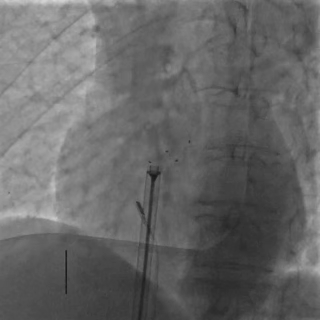

前顶钢缆和鞘管,牵拉成型线进行锁定,DSA下可见4个Mark点聚拢

牵拉试验

DSA下后退鞘管,轻轻牵拉钢缆,4个Mark点相对位置未发生变化,证明锁定成功

DSA下可见4个Mark点相对位置保持不变,整体随心博移动